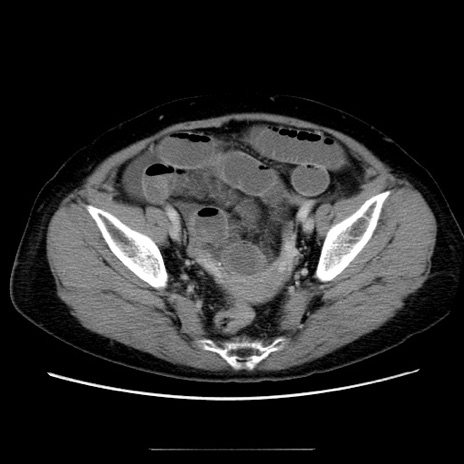

症例5(横断像)

【症例】70歳代女性

【主訴】お腹が張る

【現病歴】1週間くらい前から腹部膨満の自覚あり。昨日夜から増悪したため、本日救急外来受診。

【身体所見】意識清明、BT 36.5℃、BP 165/106mmHg、HR 80bpm、SpO2 98%、腹部:膨満、軟、自発痛・圧痛なし、触診にて不快感あり、腸蠕動音:減弱

【データ】WBC 12600、CRP 1.04